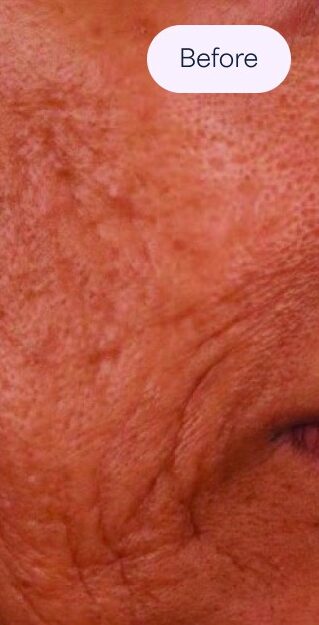

Anwendungsgebiete des SkinPen®

Aknenarben

Tiefe Grübchen (in der Regel weniger als 2 mm breit).

Sie dringen in die Haut ein und verleihen ihr den Anschein, als sei sie von einem Eispickel durchstochen worden.

Eckige Narben mit scharfen, vertikalen Kanten.

Kann flach oder tief sein.

Am häufigsten an den Wangen und Schläfen zu finden.

Verursacht durch Schädigungen unter der Hautoberfläche.

Verleihen Sie der Haut ein wellenartiges Aussehen.

Sie sind tendenziell breit und flach.

Weiblich, Behandlungen: 6. Fotos mit freundlicher Genehmigung von: Cathy A. Presnick, staatlich geprüfte Kosmetikerin; A Perfect Complexion, LLC, Melbourne, Florida